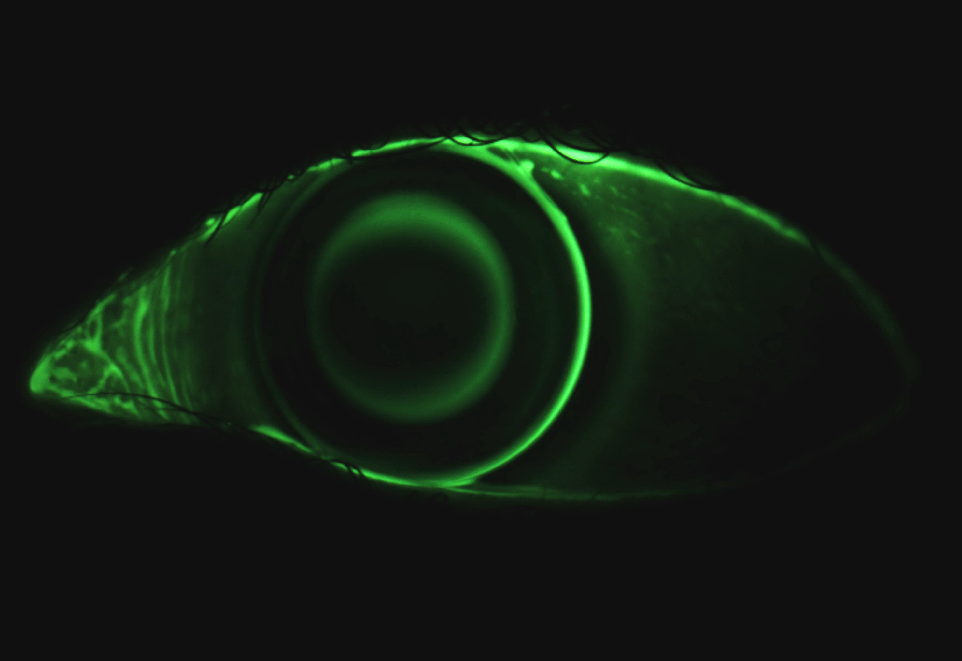

L’ortocheratologia è una tecnica contattologica innovativa per la compensazione dei difetti visivi attraverso l’uso di specifiche lenti a contatto, progettate per indurre un rimodellamento temporaneo dell’epitelio corneale, in questo modo in la cornea viene indotta ad assumere la forma di una lente in grado di correggere il proprio difetto visivo; pochi micron di differenza sono sufficienti per ottenere una visione nitida e stabile per tutto il giorno.

Queste speciali lenti a contatto sono progettate per essere indossate di notte durante il sonno e rimosse la mattina dopo il risveglio quando potrai vedere come se non avessi alcun difetto visivo, in modo nitido e naturale per tutto il giorno, prima di coricarti la sera dovrai ovviamente indossarle nuovamente.